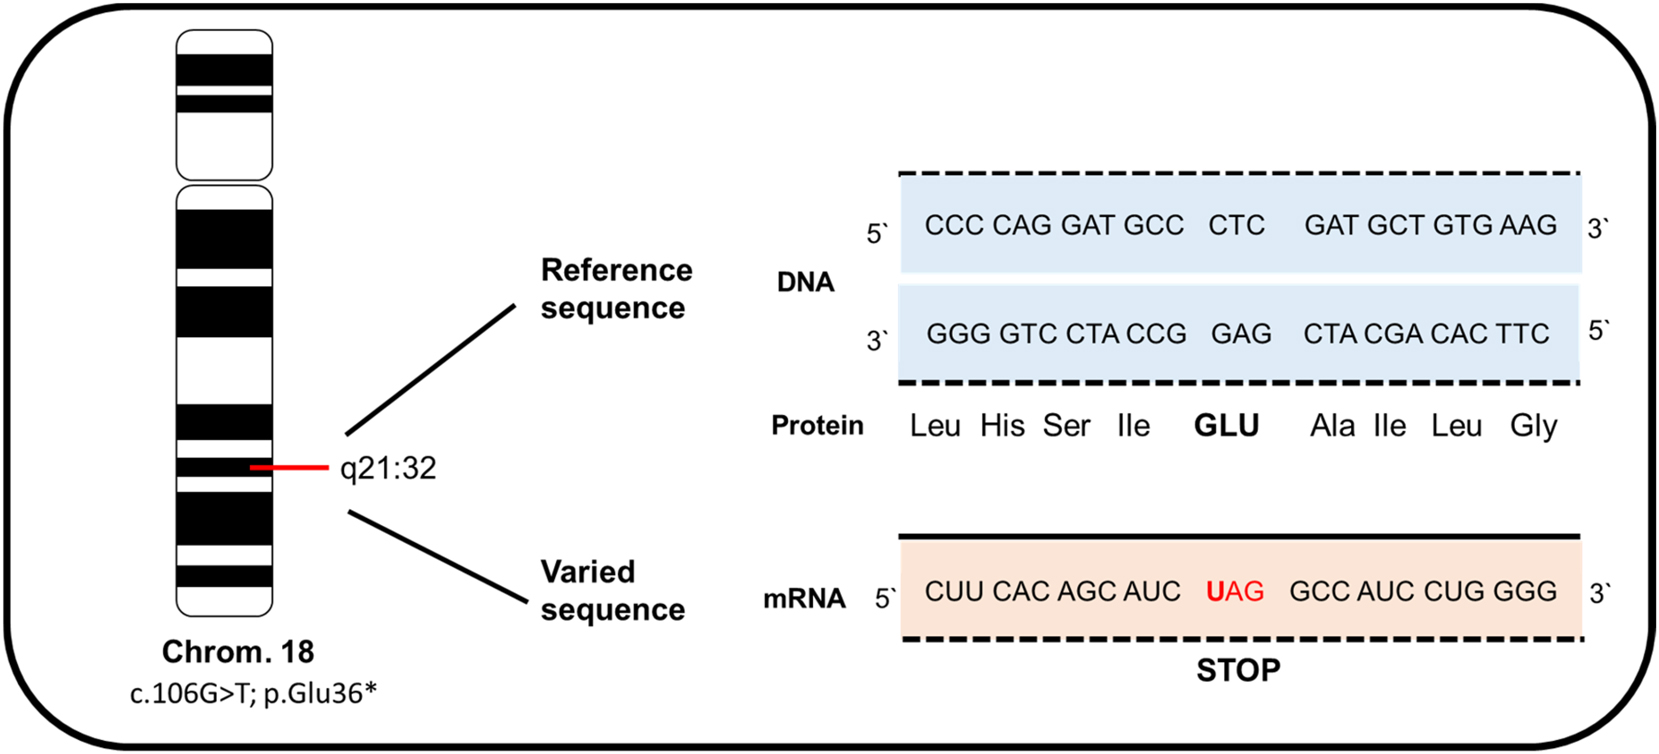

The diagnosis of anophthalmia was confirmed by fetal magnetic resonance imaging (MRI) (Figure 3A). Clinical exome sequencing (CES) was performed after amniocentesis, revealing a novel homozygous autosomal recessive mutation in chromosome 18. According to genetic analysis, this RAX mutation (c.106G>T; p.Glu36Ter) within the RAX gene formed a stop codon, causing a nonsense-mediated mRNA decay and resulting in a loss of function of the protein (Figure 4).

Illustration of the homozygous variant c.106G>T; p.Glu36* in the RAX gene located on chromosome 18 from our patient. This mutation leads to the formation of a stop codon, causing a nonsense-mediated mRNA decay and resulting in a loss of protein function.

During the development of the vertebrate eye, a series of intricate steps must occur to form the visual system, including the specification of the anterior neural plate, the evagination of the optic vesicles from the ventral forebrain, and the cellular differentiation of both the lens and retina. Mathers et al. found that Homeobox-containing genes, particularly RAX, play a critical role in forming vertebrate and invertebrate eyes. The misexpression of the Retinal homeobox protein Rx, also known as retina and anterior neural fold homeobox RAX that is located on chromosome 18 (OMIM No. #601881), can have profound effects on eye development and morphology, as this gene is responsible for the proper differentiation of the lens and retina [1]. There are a few studies conducted by Voronina et al., Lequeux et al., Abouzeid et al., and Chassaing et al. [6], [7], [8], [9], [10] that provide valuable insights into the various RAX gene mutations showing patients’ cases with congenital eye malformations. Voronina et al. screened 75 individuals with clinical anophthalmia and microphthalmia for mutations in the RAX gene. They found that a 12-year-old autistic boy with clinical anophthalmia of the right orbit and microphthalmia with sclerocornea of the left eye had compound heterozygosity for a truncated allele (Q147X; 601881.0001) and R192Q mutation (601881.0002), both within the homeodomain of the RAX gene [6]. Lequeux et al. also identified compound heterozygosity for a deletion (601881.0003) and a nonsense mutation (601881.0004) in the RAX gene in a 2-year-old Algerian girl with bilateral clinical anophthalmia [7]. In two unrelated Egyptian families, Abouzeid et al. found three cases where individuals had bilateral anophthalmia with associated severe brain anomalies. In all three cases, homozygosity for the same splice site mutation (601881.0005) in the RAX gene was identified [8]. In a study by Chassaing et al., four patients with biallelic mutations (611038.0006) in the RAX gene were identified from a cohort of 150 patients with isolated or syndromic microphthalmia or anophthalmia [9]. Brachet et al. recently reported that the loss of expression of the RAX gene leads to endocrinological imbalances such as hypothyroidism, hypopituitarism, and diabetes insipidus, as well as bilateral lip and cleft palate. They identified a 1-bp deletion (611038.0007) in the RAX gene as well as a missense mutation of unknown significance in RAX in a 10-month-old boy with bilateral anophthalmia, cleft lip and palate, and hypoplasia of the anterior pituitary gland [10]. Additionally, Brachet was able to show using an animal model with knockout mice that experimentally generated RAX-null mice showed similar abnormalities in their newborn pups, such as a loss of ventral forebrain structures and the pituitary, basosphenoid bone, and palate.